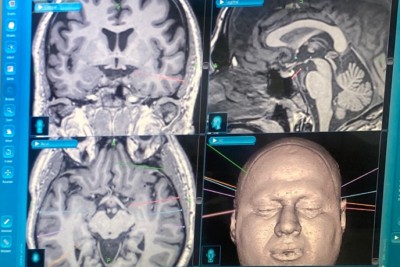

صحة الشرقية: ثلاثة طرق لتشخيص المصاب بالتصلب المتعدد

أوضحت صحة الشرقية أن هناك ثلاثة طرق لتشخيص المصاب بالتصلب المتعدد، وذلك ضمن جهودها للتوعية بأمراض الجهاز العصبي. وأوضحت الصحة الشرقية عبر حسابها الرسمي على موقع التواصل الاجتماعي ”تويتر“، أن طرق تشخيص المرض تتضمن التاريخ المرضي والفحص السريري، وأشعة الرنين المغناطيسي للدماغ والحبل الشوكي، وعمل عينة الظهر ”البزل القطني“ لفحص سائل النخاع الشوكي. وأشارت إلى أنه يتطلب أحيانًا إجراء بعض الفحوصات المختبرية والأشعة الأخرى للمساعدة على استبعاد الأمراض والحالات الأخرى التي تتميز... |